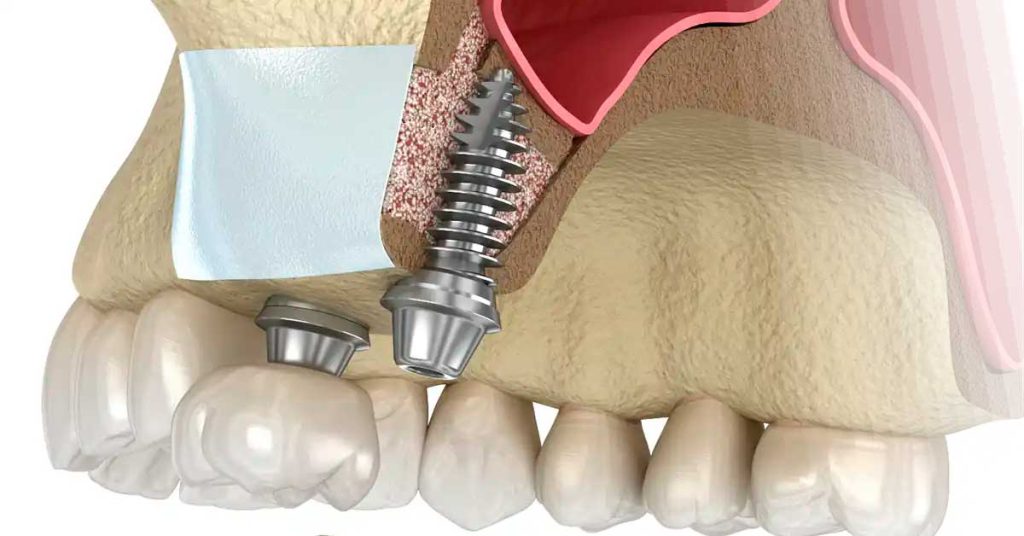

Ideal para a reposição de um ou mais dentes perdidos sem desgastar os dentes vizinhos. Utilizamos pinos de titânio de alta pureza (incluindo a linha premium Straumann) que atuam como raízes artificiais, preservando a estrutura óssea e garantindo uma estética idêntica aos dentes naturais.

Enxerto Ósseo e Levantamento de Seio Maxilar

Para que um implante dentário seja duradouro, ele precisa de uma base óssea sólida. Muitos pacientes acreditam que não podem realizar o sonho de dentes fixos por “falta de osso”, mas na Clínica Muglia, utilizamos técnicas avançadas de reconstrução para viabilizar esses casos, mesmo em cenários de atrofia severa.

O Enxerto Ósseo é um procedimento de alta precisão onde utilizamos biomateriais de padrão internacional para preencher áreas afetadas por extrações antigas ou infecções. Em casos onde a perda óssea ocorre nos dentes superiores posteriores, realizamos o Levantamento de Seio Maxilar, uma técnica que recupera a altura óssea necessária para a instalação segura dos implantes.

O Diferencial da Clínica Muglia: Cicatrização Acelerada (L-PRF) Para tornar o processo mais rápido, utilizamos o Gel de Plaquetas (L-PRF). Coletamos uma pequena amostra de sangue do próprio paciente, que é centrifugada para concentrar fatores de crescimento. Esse material biológico acelera a cicatrização, reduz o inchaço e estimula a regeneração óssea natural.